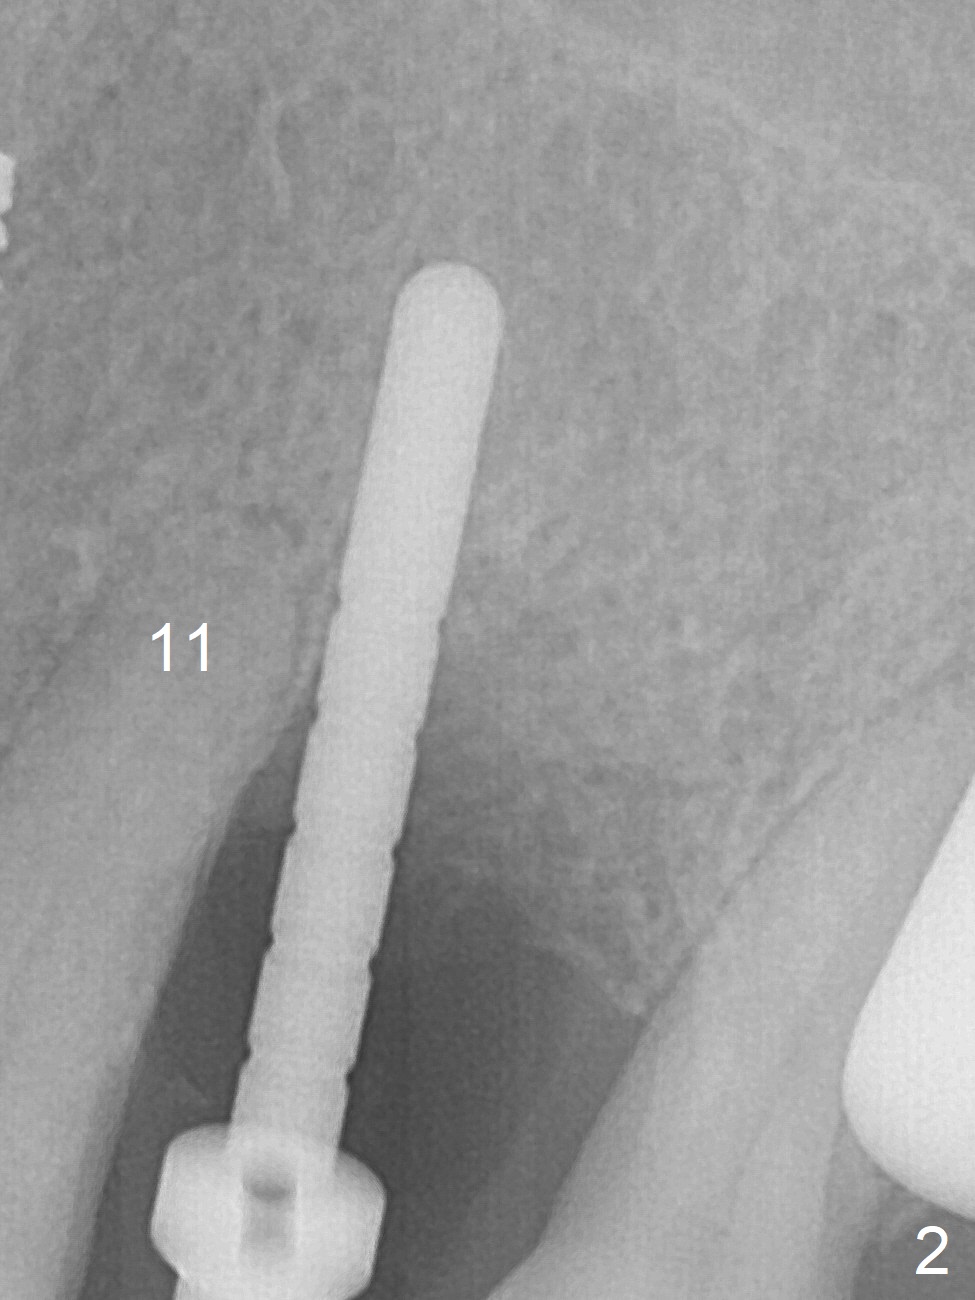

A few days prior to surgery, the tooth #12 developed abscess, self controlled by water pik (Fig.1 *). The buccal plate is defective. Initial osteotomy is close to the root of the tooth #11 (Fig.2). After adjustment of the trajectory and the depth of osteotomy (Fig.3), a 3.8x15 mm dummy implant is placed (Fig.4,5). In spite of a shorter implant (3.8x13 mm) placed deeper, approximately 7 mm implant threads are not covered buccally by the native bone (Fig.6 red dashed line). If the implant were placed deeper, the crown/implant ratio would become more unfavorable (abutment screw loosening, Fig.7). Since a mill abutment (4.5(2) mm) is inserted before Vanilla Graft, the deepest portion of the socket is unfilled (Fig.7 *). With meticulous use of a long explorer and additional allograft, the space is closed (Fig.8 *). The buccal plate collapses with apparently fistula formation 2 months postop. The patient removes the provisional for cleaning. It appears that the mill abutment is buccally placed and needs heavy reduction. The mill abutment is loose 2 months 10 days postop. When it is retightened, it tilts distal. Bone remains around the implant 6 months postop (Fig.9). Without a provisional at #12 for 5 months, the tooth #13 appears to have been shifted mesially (Fig.10 arrow). The mill abutment at #12 changes to a healing one. A lingual button is placed in the mesial surface of #13. Splinted provisional is fabricated with supraocclusion at #14 and 15 as an anchor (implants). The tooth #13 is being distalized with power chains. Limited ortho is finished nearly 2 months post banding (Fig.15,16).